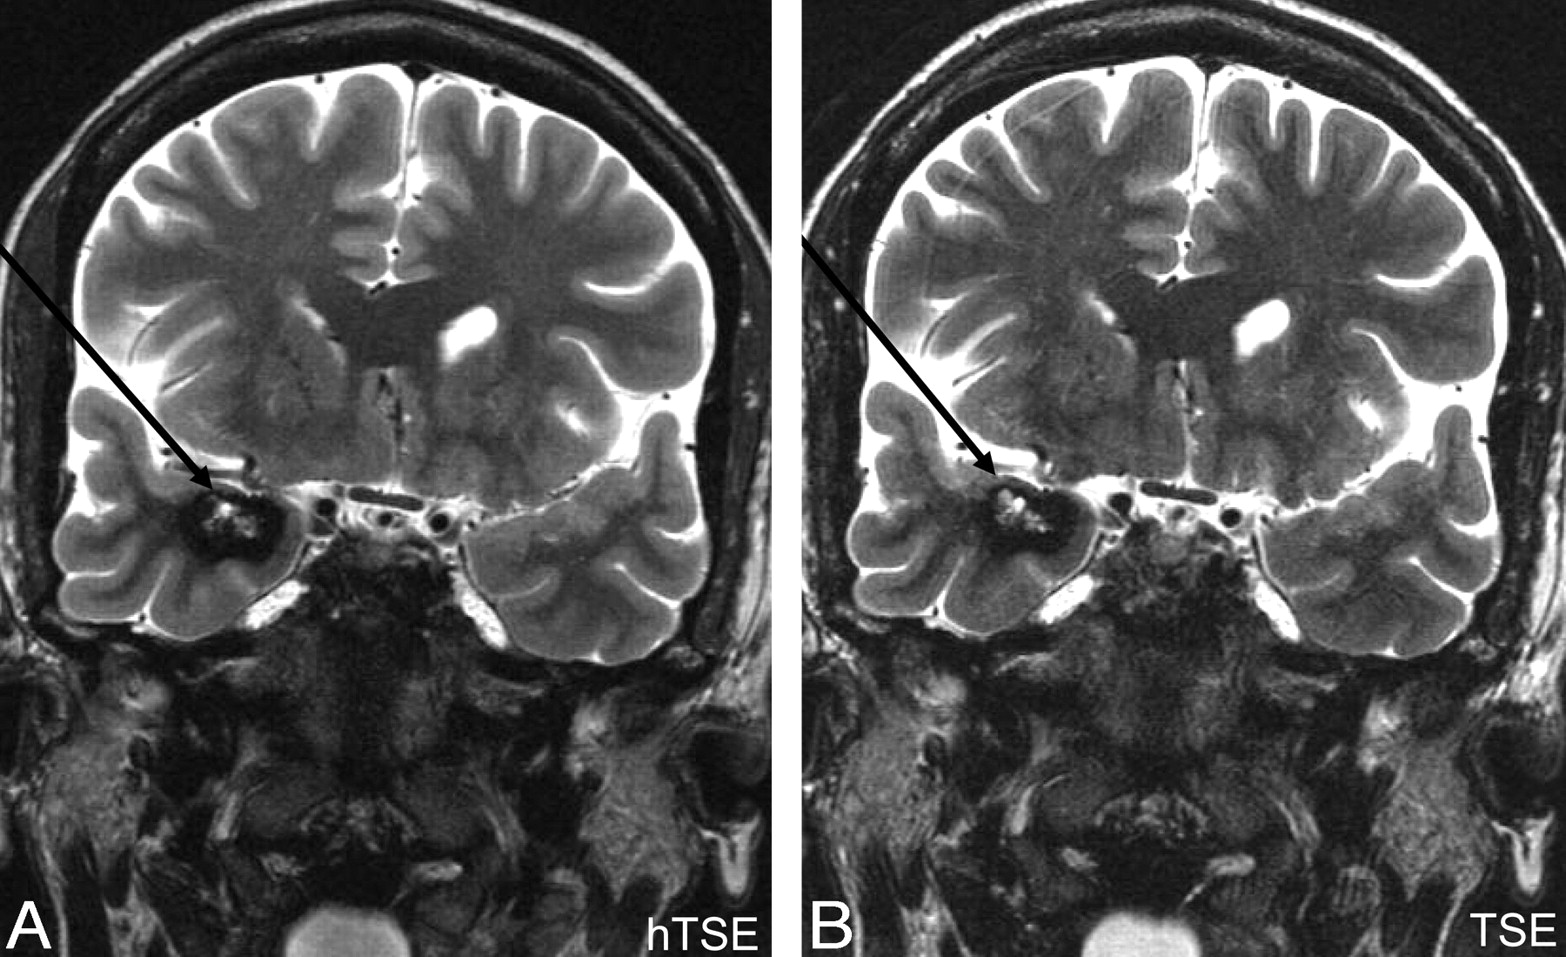

Representative cases, including 2 hyperintense lesions (a posttraumatic contusional state and a hippocampal sclerosis) and 1 hypointense lesion (cavernoma), are shown in Figs 4–⇓6, respectively.

A, HyperTSE (hTSE). B, TSE180°. A right mesiotemporal cavernoma (arrows) consisting of a hypointense hemosiderin rim and a central hyperintense matrix containing methemoglobin is clearly depicted in both sequences. It is important that both parts of blood degradation products are depicted; this depiction was successful for both sequences. The diagnosis was confirmed by surgery.